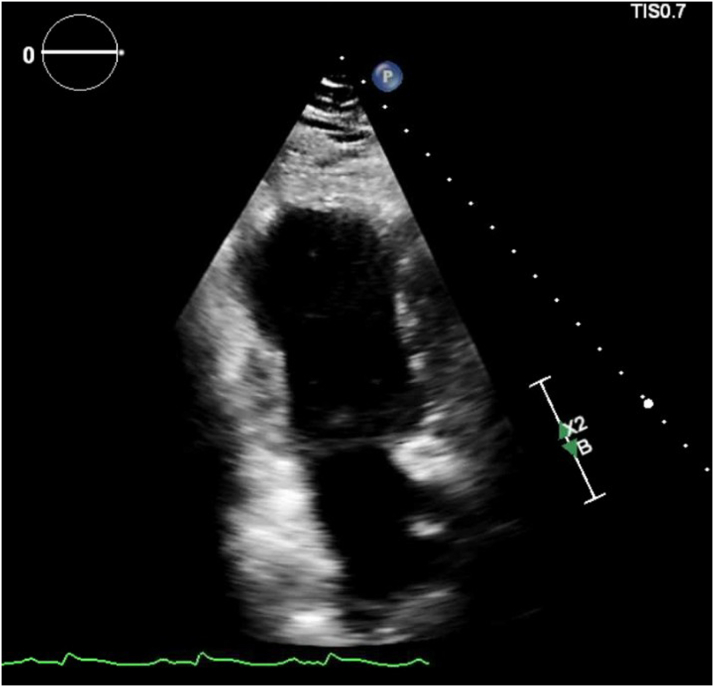

The coronary angiogram did not show any obstructive coronary lesions, and right heart catheterization revealed an elevated pulmonary capillary wedge pressure of 30 mm Hg, a cardiac index of 1.4 L/min/m2, and an elevated right atrial pressure of 15 mm Hg, consistent with new heart failure and cardiogenic shock of nonischemic etiology. The echocardiogram showed a left ventricular ejection fraction (LVEF) of 15% to 20%, with mid to apical wall hypokinesis (Figure 2, Video 1).